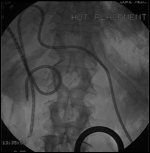

FIGURE 1

Intraluminal Transcatheter Brachytherapy

Takamura summarized the results in 88 patients undergoing metallic stenting with EBRT/Ir-192 therapy for unresectable disease. Forty-six (49%) patients developed reobstruction at a mean duration of 11.6 months posttherapy. In half of these patients, tumor recurrence resulted in obstruction. Cumulative biliary patency rates at 1 and 3 years were 52% and 29%, respectively. For 20 patients undergoing autopsy, obstruction from debris, sludge, stones, and bleeding was observed in 17.[42] Figure 1 shows the placement of intraluminal Ir-192 seeds via a percutaneous transhepatic biliary drainage tube.